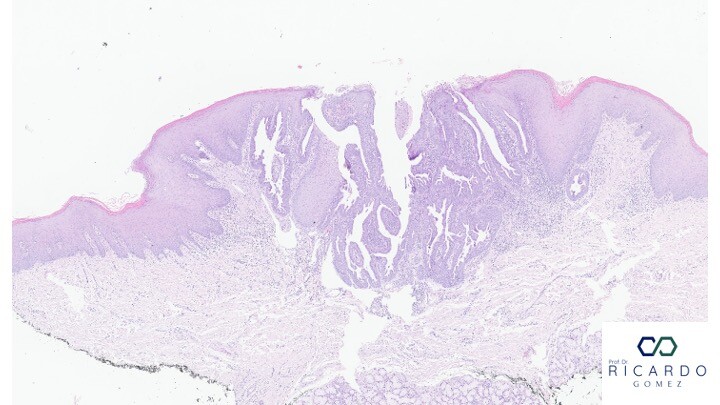

Figura 1- Sialoadenoma papilífero de glândula salivar menor. Observa-se crescimento exofítico com projeções papilíferas epiteliais contínuas com a mucosa de revestimento.

Microscopicamente, o SAP mostra padrão de crescimento papilar, com projeções epiteliais exofíticas e endofíticas contínuas com os ductos salivares. As projeções epiteliais são compostas por duas ou mais camadas celulares, frequentemente com diferenciação ductal, escamosa ou oncocítica. As papilas comunicam-se com a mucosa de superfície e possuem eixos fibrovasculares. O estroma subjacente é fibroso, com infiltrado inflamatório crônico de intensidade variável. A pesquisa da mutação BRAF V600E pode auxiliar o diagnóstico em casos de morfologia atípica ou lesões mimetizantes.